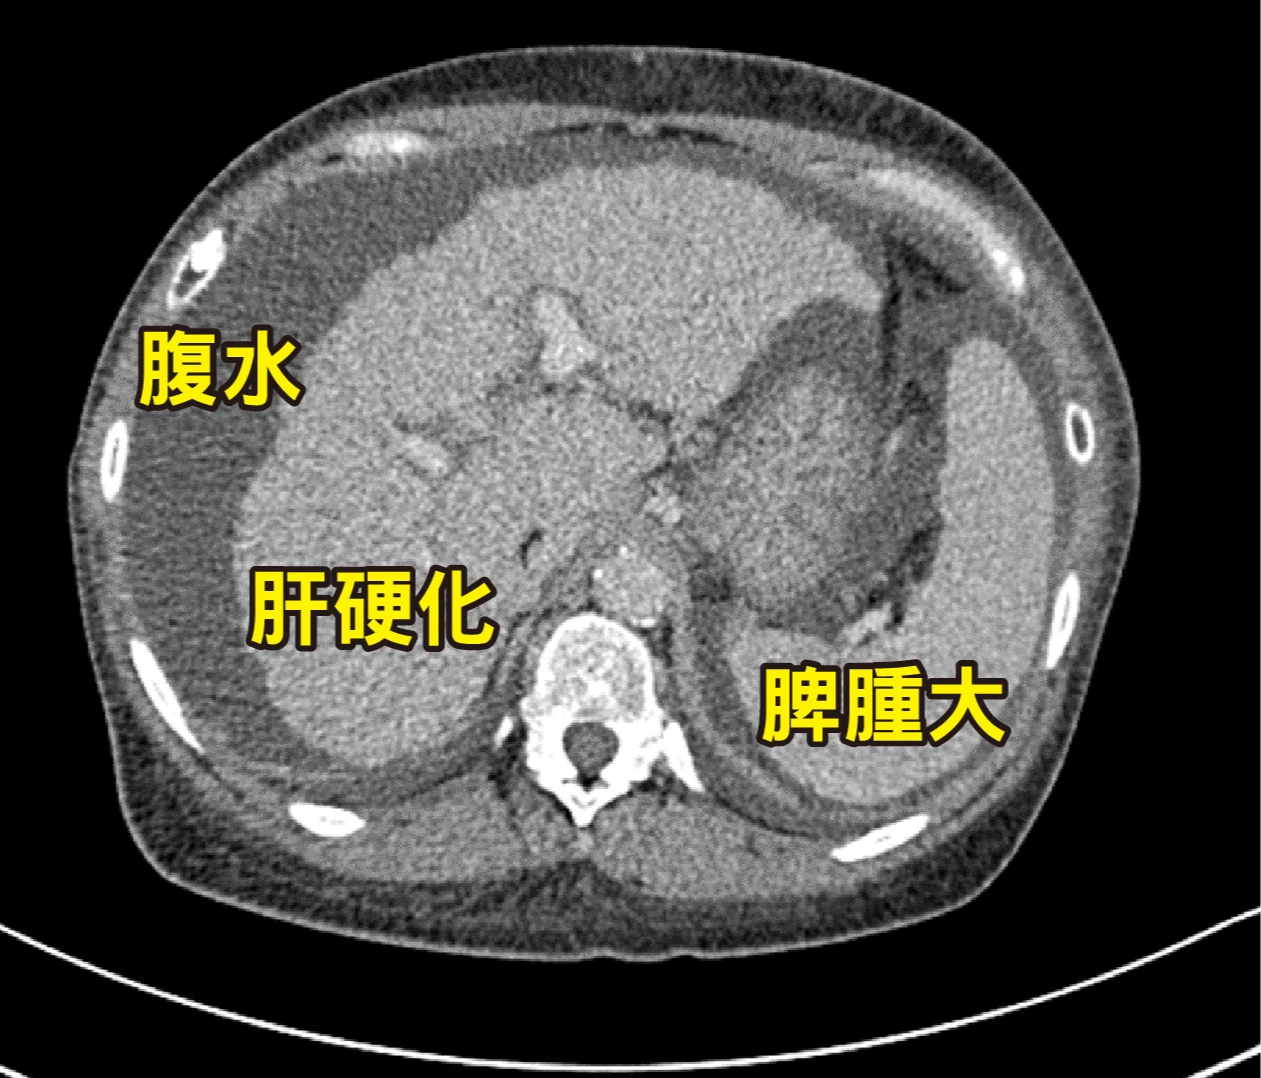

肝臟表面原本應該是平滑的,但米德莉的肝臟影像,卻呈現像苦瓜一樣凹凸不平的外觀,她的腹部還有積水,脾臟也有腫大的情形。

患者重度肝硬化 術中極易發生大出血

林俊昌指出,她的病程已達重度肝硬化的C級,長期門脈高壓,導致腹腔內側支循環異常發達且代償性擴張,加上肝功能衰竭引發的凝血因子合成障礙,使得術中極易發生大出血的高風險,致使移植手術更加困難,在術前評估時,團隊嚴陣以待務必做好萬全的準備。